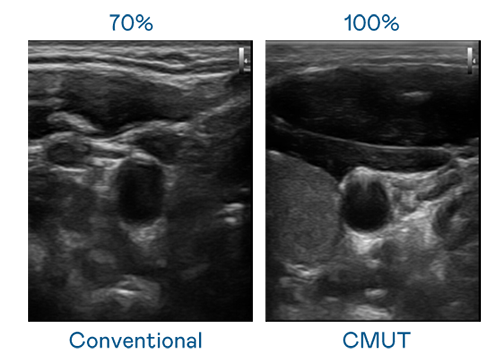

CMUT 技術是一種用電容式微機電元件來產生超音波訊號的技術。與傳統 PZT 壓電式技術相比,CMUT 頻寬增加 30%,更寬頻的超音波訊號讓影像解析度大幅提升,是實現高影像品質醫療超音波掃描、促進精準醫療發展的關鍵技術。

大頻寬帶來超清晰影像

超音波影像的解析度高低,首先取決於探頭能發出的訊號頻寬。爱游戏 CMUT 可提供高清晰的超音波訊號,提供高頻寬、高靈敏度、影像紋理細節更高的超音波影像,協助醫護人員縮短影像判讀時間及利用精準的醫療影像進行診斷。